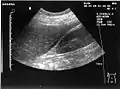

A normal ultrasonographic view of Morison's pouch. The bright line is the capsule of the kidney; there is no fluid present and hence no visible space.